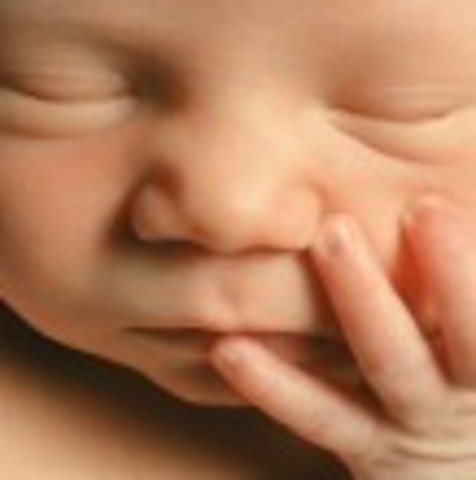

• Week 12: Fingernails and Toenails Appear

Week 12: Fingernails and Toenails Appear

The fetus is beginning to move a lot more. The face is also beginning to look a lot more like a baby's face. The pancreas is beginning to function.